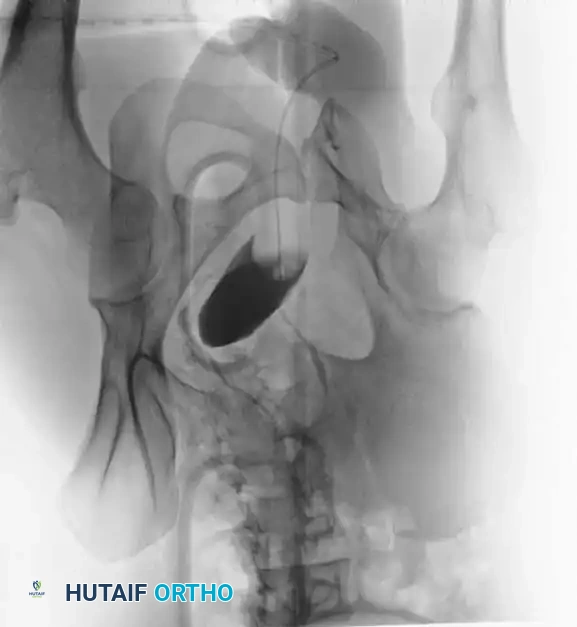

Hemorrhage Control and Pelvic Binding

If the patient is hemodynamically unstable, immediate circumferential pelvic wrapping is indicated. A pelvic binder or tightly wrapped sheet must be centered over the greater trochanters—not the iliac crests—to effectively close the pelvic volume and provide a tamponade effect.